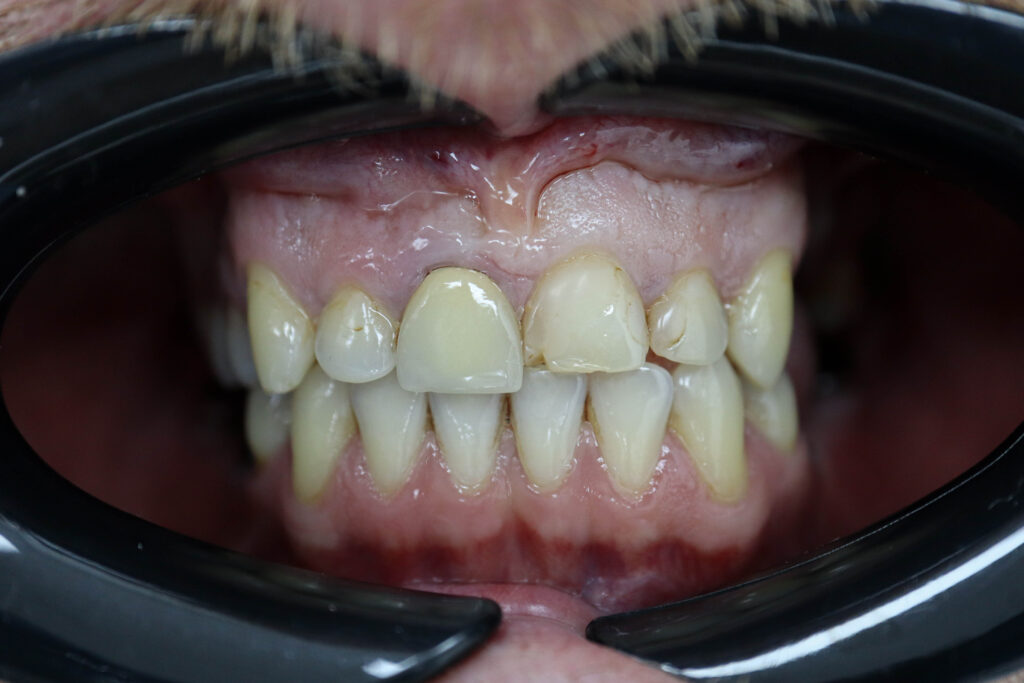

Ситуация до лечения

Пациент обратился с жалобами на эстетические недостатки.

Диагноз: Частичная адентия

Ситуация до лечения Бутримович